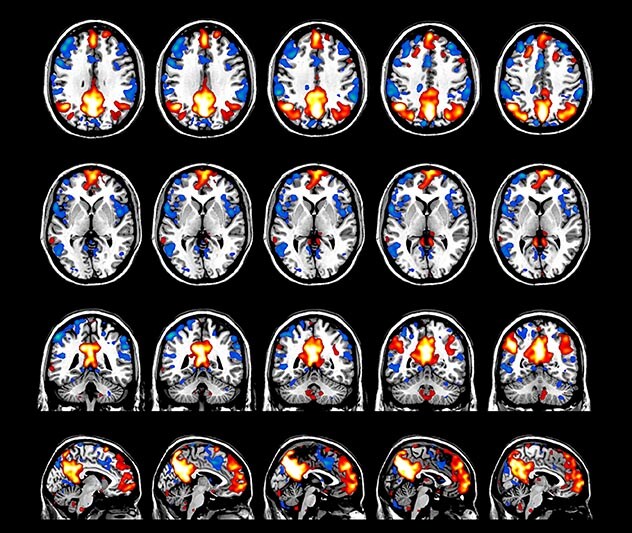

BOLD fMRI activation, depicted in color, of left anterior insula (MNI plane z = 8 mm) in a single subject by a contrast between viewing and matching faces with negative emotion (angry, sad, scared) versus happy faces. The voxelwise threshold is p < 0.001, and colored voxels survive false discovery rate correction to p < 0.05. The activated voxels in color are overlaid on the subject's own 3D-TFE image displayed in grayscale, after transforming the data to MNI space. The fMRI pulse sequence was a single shot FFE echo planar acquisition using MultiBand SENSE factor 6, dS SENSE factor 1, isotropic voxel size 2.4 mm, 60 transverse slices, TR 950 ms, TE 30 ms, flip angle 52 degrees, 517 dynamic scans, total scan duration 8:21 minutes. Image provided by James M. Bjork, PhD, Associate Professor of Psychiatry at VCU.

Imaging was performed using Ingenia 3T CX with a 32ch dS Head coil, TR 1.6 sec, TE 35 ms, voxel size 3.1 x 3.1 x 3.1 mm, 46 slices and Multiband SENSE factor 2. Image provided by Dr. Gispert

Default mode network as discovered by resting state fMRI in one participant of the ALFA cohort [7]. rs-fMRI allows us to find networks of brain regions with highly correlated activity and sustaining distinct brain functions. The default mode network (in warm color scale) is active when the brain is focused on introspective thinking and has been shown to be altered in Alzheimer’s. Interestingly, brain areas of this network are known to show abnormal levels of one of the pathological hallmarks of Alzheimer’s (b-amyloid deposition) in preclinical stages. We want to better understand the alterations of these brain networks in preclinical stages of Alzheimer's and explore their potential use as biomarkers.

Emotional n-back task combines a test of working memory with the use of emotive (faces) and neutral (places) images. The contrast in the images is between the activity when faces are presented compared to places, showing activation in the amygdala, fusiform, and occipital face areas.

Processing based on the Human Connectome Project (HCP) pipelines. The high resolution of the fMRI data allows extraction of the cortical surface, with minimal averaging of non-cortical signal. Surface based analysis provides improved cross-subject alignment, and prevents signal contamination between adjacent sulci.

Group analysis of 88 9- and 10-year olds part of ABCD, all scanned at UVM on Philips Achieva 3.0T dStream. Scale runs from red p=0.001 to yellow p<10ˆ-5. Images provided by Dr. Watts.

Acquisition using the ABCD protocol for fMRI with TR 800 ms, TE 30 ms, flip angle 52°, 2.4 mm isotropic imaging resolution with a 216×216×144 mm3 field of view using a MultiBand acceleration factor of 6 (60 slices, no gap). Two runs of 5 minutes per subject.